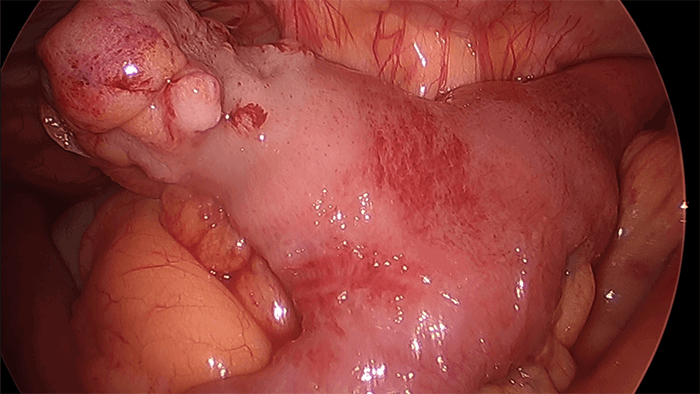

A 60-year-old female patient presented to the emergency room complaining of nausea and vomiting for three days, along with right upper quadrant (RUQ) abdominal pain. The patient described the RUQ pain as a gnawing, spasm-type pain that became severe at the time. The patient then underwent an ultrasound of the RUQ, which revealed mild dilation of CBD at upper limits of normal, no gallbladder wall thickening, and no cholelithiasis. Patient was also sent for an abdominal X ray (Figure 1) and CT of the abdomen and pelvis (Figure 2), which showed a partial distal small bowel obstruction (pSBO) with a normal gallbladder.

Figure 2. Abdominal CT in ER, showing pSBO